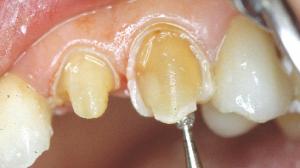

Préparation de la 23. Réalisation d'un sillon qui suit le périmètre de la face vestibulaire avec une fraise boule de 1mm.

La fraise boule est enfoncée à moitié. Ce sillon aura donc une profondeur d’environ 0,5 mm. Au collet, le sillon est pour le moment nettement éloigné de la gencive.

Des tranchées verticales sont réalisées avec la même fraise boule et à la même profondeur que le premier sillon (0,5mm).

Une ou plusieurs tranchées horizontales réunissent les tranchées verticales.